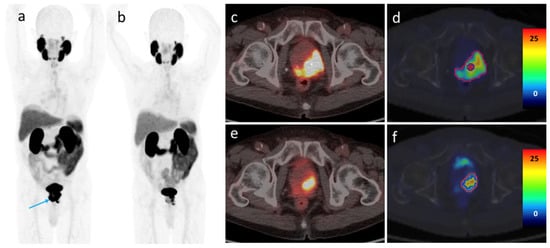

3.4. [68Ga]Ga-PSMA-11 PET/CT Imaging after ADT